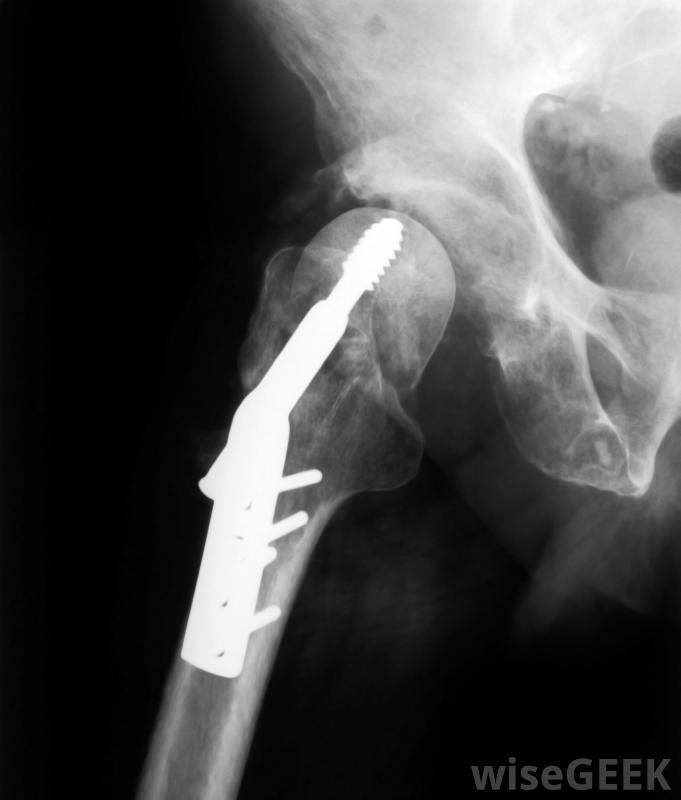

钛棒、螺钉和钢板可用于重建骨折或其他损伤后的骨骼或关节。用于医疗用途的特定钛棒通常取决于患者的受伤情况以及钛棒的稳定性或柔韧性。当强度为唯一的原因,比如用钛棒代替腿部的骨头时,骨科医生通常会使用钛合金制成的棒。因为纯钛比钛合金棒更灵活,这些类型的棒通常用于植入前必须成形的病人。钛合金棒通常用于大多数病人。但是,与这些类型的棒相关的摩擦率很高,因此必须不惜一切代价避免与其他钛合金棒摩擦对于需要骨科手术的儿童,通常使用膨胀钛棒这是一种可以固定在关节处的棍子,随着孩子的成长,它会随着骨头一起伸展。虽然这是对仍在成长中的孩子最好的棒型,膨胀钛棒只能用来代替腿部骨骼等身体中的大骨头,使用膨胀棒也可以减少后续手术的发生,因为它会在一定程度上随孩子成长,甚至虽然可以随时使用扩张棒,但有时使用非扩张棒是必要的。如果非扩张钛棒用于任何患者仍在生长的手术中,有必要进行多次手术来更换鱼竿。如果在随后的手术中没有更换鱼竿,这可能会阻碍孩子的成长,因为鱼竿不允许他或她的身体自然生长。